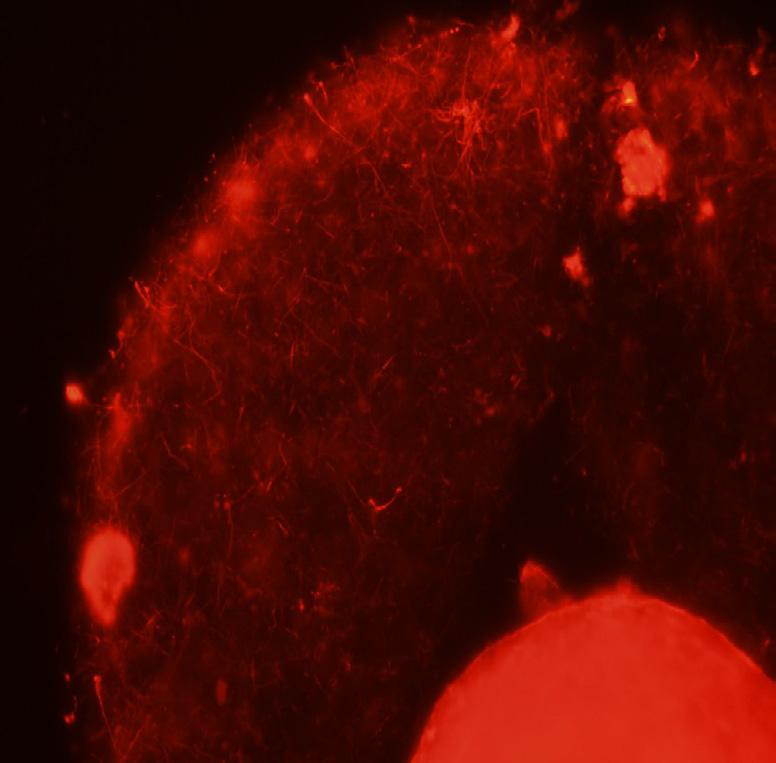

Communication between patients, physicians, nurse coordinators and embryologists is the key to success at the CHR. Timing from cycle start to embryo transfer not only depends on an interactive platform between all participants but also on the biological underpinnings that enable sperm and egg to collaborate in the process of fertilization and embryo development. This image from professor Albertini’s archives documents a case where upon retrieval this human oocyte was found to be immature and therefore not ready for fertilization. It happens that many patients get to retrieval only to yield a small percentage of oocytes that have not been able to fully mature. Not to worry, the embryologists who recognize this situation will give such eggs a “second chance” by culturing them overnight upon which about 50% of oocytes will have reached the mature metaphase-2 state. This picture reveals a telltale sign of the problem and if you look closely, you may be able to see many fine threads sending information from the surrounding cumulus cells through the black zona pellucida that may, or may not signal the oocyte to mature.

If we take a closer look inside the shell covering of the oocyte (red sphere lower right corner) these threads serve as telephone cables transmitting information from the cumulus cells into the oocyte. Just what kind of information is conveyed to the oocyte is under investigation but Dr. Albertini and colleagues over the years have discovered that important fuels like ATP are among the critical molecules the egg receives during ovulation that will propel the activities of the embryo following fertilization.

This elaborate communication system between the oocyte and its companion cells is not unique to humans. This figure illustrates using confocal microscopy one of the first images taken from a rhesus monkey oocyte that was collected just prior to the animal undergoing ovulation. Only a small portion of the oocyte is visible within the zona pellucida but it is clear that each of the surrounding cumulus cells are interconnected with each other and with the oocyte by these specialized information bearing structures. Here at CHR we take pride in continuing our research on the role communication plays in determining the quality of the oocytes our patients provide on the long and winding road to parenthood.